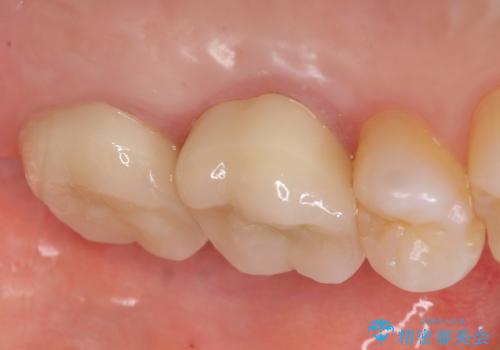

- 他院にて治療した左上奥歯の疼くような痛みが引かないため当院にいらっしゃった方の症例です。

検査の結果左上6に打診痛、根尖部圧痛、根尖病変を認めたため、再根管治療を行ったところ症状が緩解したため、オールセラミッククラウンによる補綴を行いました。

左上7は治療を希望されなかったため、オールセラミッククラウンによる補綴のみを行いました。

今回用いたオールセラミッククラウンはジルコニアフレームという白い素材の上にセラミックを盛っているため、審美性が非常に高いのが特徴です。

また、ジルコニアは人工ダイヤモンドの材料にも使われているほど高い強度を持っており、そのためオールセラミッククラウンは審美性だけでなく、奥歯やブリッジの補綴も可能とするクラウンです。